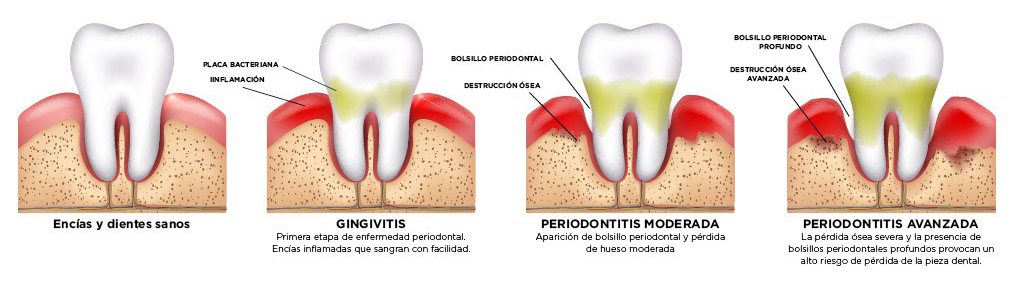

El periodonto es el conjunto de tejidos especializados (encía, ligamento periodontal, cemento y hueso alveolar) que preservan, sirven de soporte y mantienen estables los dientes. Las enfermedades periodontales son infecciones bacterianas del periodonto, es decir del conjunto de tejidos especializados (encía, ligamento periodontal, cemento y hueso alveolar) que preservan, sirven de soporte y mantienen estables los dientes.

La gingivitis y la periodontitis son formas de la enfermedad periodontal que producen encías rojas, inflamadas y que sangran fácilmente. La gingivitis, la fase inicial de la enfermedad periodontal, se produce por la acumulación de placa bacteriana que se adhiere a los dientes y de no ser tratada correctamente puede evolucionar a periodontitis. El tratamiento inmediato, por lo general, revierte los síntomas de la gingivitis y previene la evolución a periodontitis de las encías y la pérdida de dientes, el mismo comprende cavitación y profilaxis profesional, restauración de ser necesaria, acompañada de una rutina diaria de buena higiene buco dental y de control periódico profesional.

La periodontitis se caracteriza por la destrucción progresiva del aparato de soporte de los dientes. Sus principales características son la pérdida de tejido periodontal, y la pérdida de hueso alveolar, la presencia de bolsas periodontales y el sangrado gingival. En el caso de no ser tratada, puede provocar la pérdida del diente, aunque en la mayoría de los casos es prevenible y tratable. El tratamiento de la periodontitis incluye tratamientos farmacológicos, así como tratamientos no quirúrgicos y quirúrgicos, como injertos y cirugía de reparación de las encías dependiendo del caso.